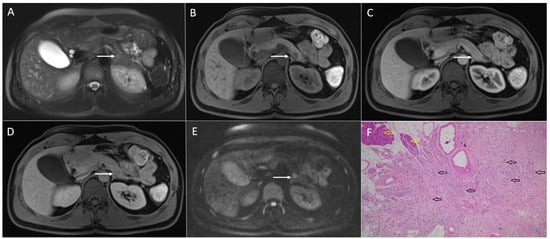

3.1. Neuroendocrine Tumors